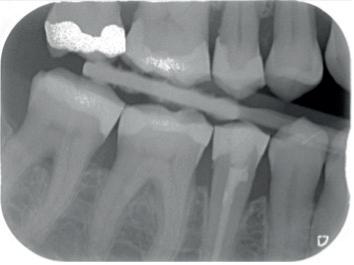

Een 62-jarige man hield in de nazorgfase een pocket van 8 mm met bloeding na sonderen mesiaal van de 36 ondanks 3-maandelijkse recall (afbeelding 2.1 en 2.3). De mondhygiëne was matig en plaque was aanwezig. Chirurgie werd geadviseerd, maar de pa-

tiënt wees dit af. Ook hier werd de pocket behandeld onder anaesthesie. De natriumhypochloriet/aminozuur-gel werd viermaal aangebracht, telkens gevolgd door ultrasone en handinstrumentatie. Tot slot werd cross-linked hyaluronzuur ingebracht. De mondhygiëne werd bijgestuurd en meneer werd gemotiveerd dagelijks interdentale ragers te gebruiken naast het poetsen.

Na zes maanden was de pocketdiepte teruggebracht tot 3 mm en was er geen bloeding na sonderen (afbeelding 2.2 en 2.4).